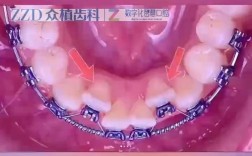

美容冠矫正牙齿是一种结合牙齿美学修复与快速矫正的技术,主要针对牙齿排列不齐、颜色异常、缺损、牙缝过大等问题,通过在天然牙体外部佩戴定制美容冠实现牙齿形态与功能的改善,其过程严谨且精细,需多步骤协同完成,具体如下:术前咨询与口腔检查这是美容冠...

“矫正打磨牙齿”这个说法通常指的是两种不同的牙科治疗,或者可能是一个误解,我来详细解释一下:🦷1.矫正牙齿(Orthodontics-正畸治疗)目的:主要解决牙齿排列不齐、拥挤、稀疏、咬合关系异常(如深覆合、深覆盖、反合/地包天...